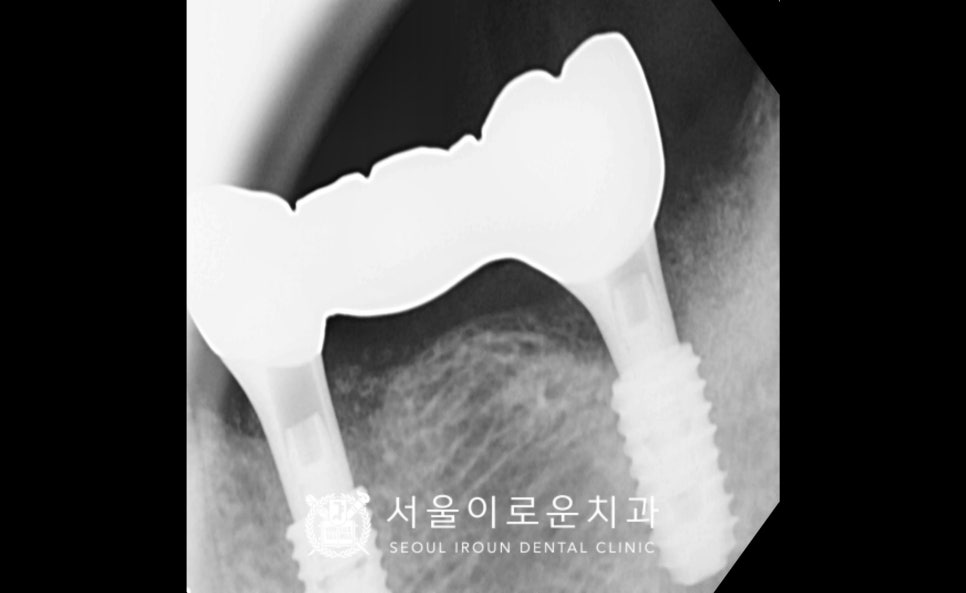

임플란트 식립 2달 반 후

osstell beacom이라는

골 유착을 확인할 수 있는 장비를 활용해

골 유착 정도가 안정 값임을 확인하고

보철 과정을 진행하였습니다.

임플란트와 크라운을 연결할 때

기둥 역할을 하는 지대주인 abutment를

환.자분 구강 내 상황에 맞는

맞춤형 지대주인

custom abutment를 체결한 뒤

자연치아의 강도와 제일 유사하고

심미적인 지르코니아 크라운으로

임플란트 보철 과정을 마무리하였습니다.